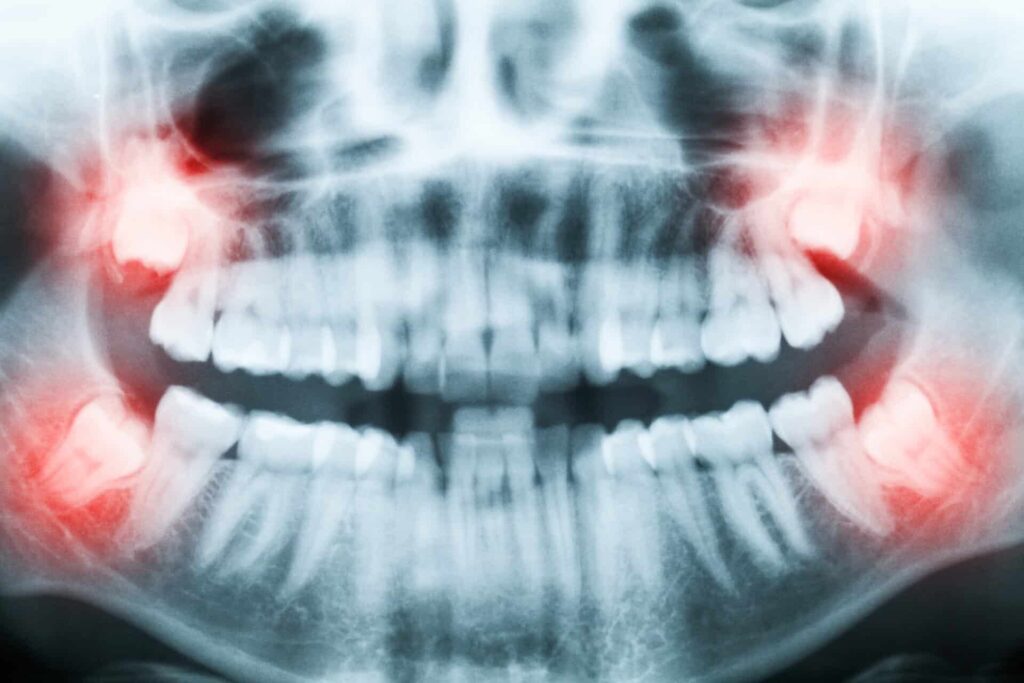

Unfortunately the wisdom teeth are prone to problems. Most people have at least one wisdom tooth that gets stuck or “impacted” trying to break through the gums. This can happen because of lack of space or the position of the tooth.

Impacted wisdom teeth can develop cavities and cause pain and discomfort; they can also damage the neighboring teeth. The gum tissue around the area of the impacted wisdom tooth can become swollen and develop gum disease.